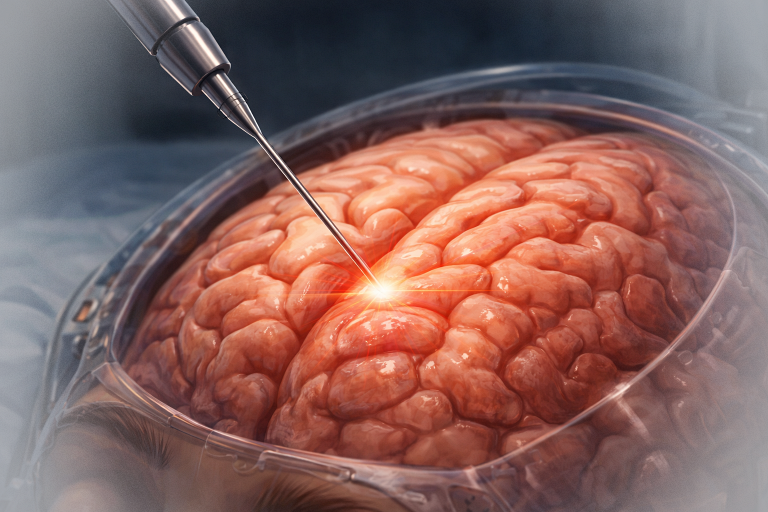

Chirurgia

Tratamentul principal este rezecția chirurgicală, dar aceasta poate fi dificilă datorită proximității unor structuri critice (hipotalamus, chiasmă optică). Opțiunile chirurgicale includ:

- Rezecția totală: este ideală, dar riscantă, deoarece poate genera deficite neurologice și endocrine permanente.

- Rezecția subtotală sau parțială: mai frecvent realizată, urmată de radioterapie pentru a limita recurența.

Chirurgia endoscopică transsfenoidală este preferată atunci când tumora are o localizare predominant selară și supraselară inferioară.

Radioterapia

Radioterapia complementară este utilizată frecvent după rezecția parțială pentru a reduce riscul de recidivă. Se folosesc tehnici avansate precum radioterapia stereotactică (Gamma Knife, CyberKnife) care limitează efectele secundare.